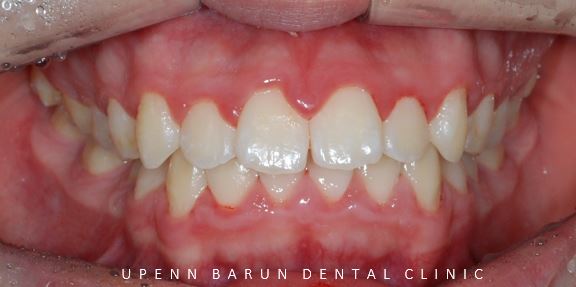

교정 전

사진에서 보시는 것처럼 윗니와 아랫니 사이에

꽤나 큰 공간이 관찰되었습니다.

악궁이 좁아 삐뚤빼뚤했던 치아들이

교정 후

발치된 공간으로 치아들이 올바르게 배열되며

교정치료가 만족스럽게 잘 마무리 되었습니다.

교정치료가 끝난 후의 사진을 보시면

교정치료 전과는 다르게

도드라져 보이던 앞니의 치열과 치축이 개선되면서

가지런하게 정리되고 예쁜 스마일로

바뀐 모습을 볼 수 있습니다. ^^**